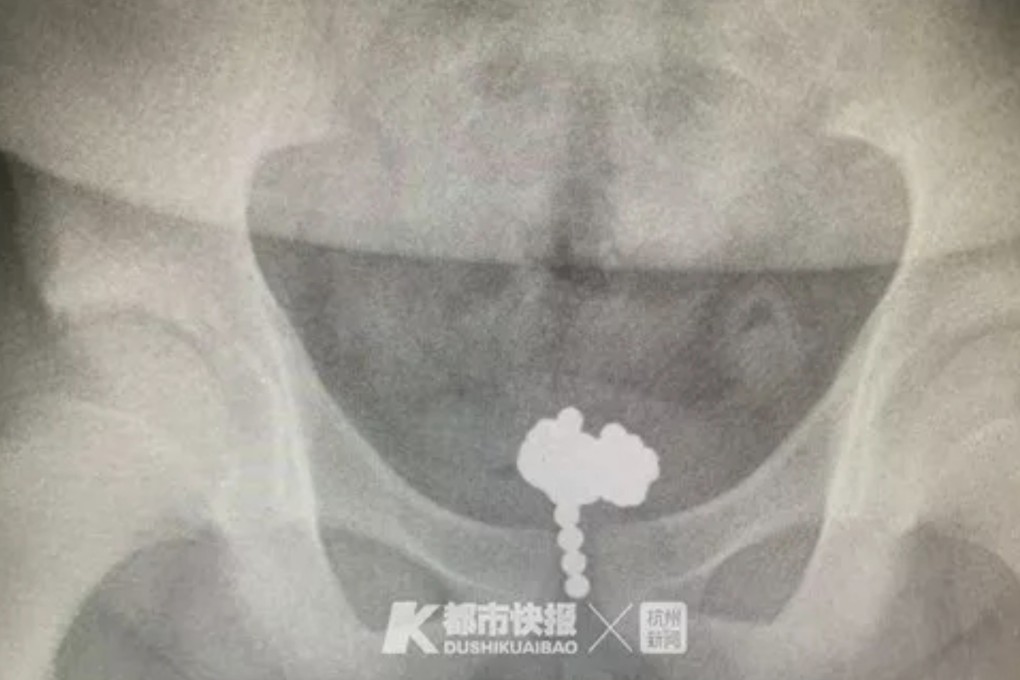

After X-ray images showed a shadow in his bladder, the boy admitted what he had done.

The 70 balls, each with a diameter of 5mm, were retrieved from his bladder in a minimally invasive operation lasting two hours.